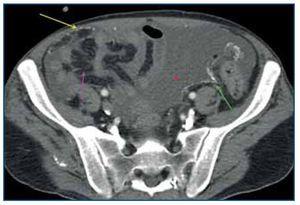

Figura 2.Tomografía computarizada abdominopélvica tras administración de contraste intravenoso, corte axial a nivel de hipogastrio. Se observan calcificaciones lineales «en sábana» del peritoneo parietal (flecha amarilla) y del peritoneo visceral (flecha verde), engrosamiento del mesenterio de las asas intestinales (flecha rosa) por el desarrollo de membranas fibróticas que retraen las asas de intestino delgado adyacentes, así como ascitis loculada (asterisco rojo) en hipogastrio.